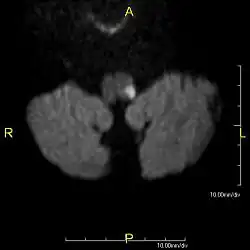

Das Wallenberg-Syndrom (synonym: Viesseaux-Wallenberg- und Wallenberg-Foix Syndrom oder auch Dorsolaterales Medulla-oblongata- oder Arteria-cerebellaris-inferior-posterior-Syndrom) entsteht durch einen Verschluss der Arteria cerebelli inferior posterior (PICA) oder der Arteria vertebralis. Als Folge davon kommt es zu einem Infarkt der dorsolateralen Medulla oblongata, die Teil des Hirnstamms ist.[1] Es ist eine seltene Form des Schlaganfalls. Die Symptome sind vielgestaltig entsprechend den jeweils betroffenen neurologischen Strukturen.

Es liegt ein Verschluss oder eine hochgradige Enge im Bereich der hinteren unteren Kleinhirnarterie (Arteria cerebelli inferior posterior) oder der Arteria vertebralis und ihrer Äste vor, die Teile des verlängerten Marks (Medulla oblongata) versorgen. Auslösend kann ebenfalls eine Hirnblutung in dieser Region sein. Es führt zu einem Infarkt am seitlichen Teil der Medulla oblongata, mit den dafür typischen Ausfallmustern. Häufigste betroffene Arterie ist die A. vertebralis.